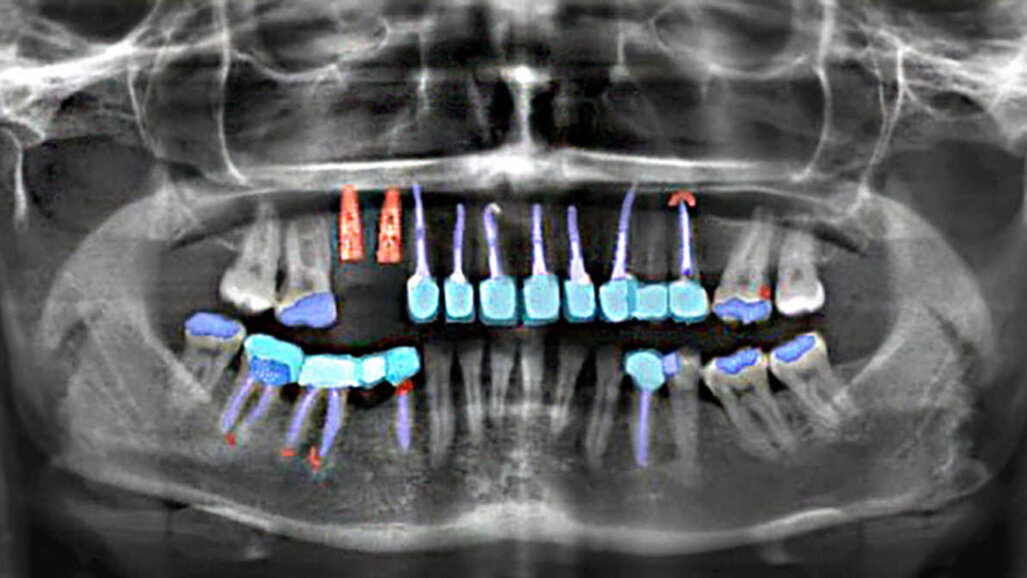

BERLIM, Alemanha: Dentistas da Charité - Universitätsmedizin Berlin, juntamente com cientistas de dados e programadores, desenvolveram o dentalXrai Pro - um programa de software que permite que os dentistas realizem a análise de radiografias com base em inteligência artificial (IA). O novo software foi projetado para ajudar os dentistas a identificar patologias e restaurações com mais precisão e em menos tempo, a fim de fornecer o tratamento ideal e melhorar a comunicação com os pacientes.

Como a maioria dos consultórios odontológicos já faz radiografias digitais, elas podem ser facilmente transmitidas para o dentalXrai Pro. Para fornecer uma imagem pré-analisada em um tempo muito curto, o software baseado em navegador acessa computadores de alto desempenho e uma ampla gama de algoritmos.

Esses algoritmos são o resultado de um treinamento aprofundado em software, usando um grande conjunto de dados de radiografias dentárias, incluindo imagens panorâmicas e bitewing. Dentistas de todo o mundo identificaram nas radiografias dezenas de milhares de alterações patológicas e vestígios de tratamentos dentários anteriores. Esses dados foram então enviados para as redes neurais artificiais, permitindo-lhes distinguir entre diferentes achados, como cáries, infecções e obturações de canal radicular.